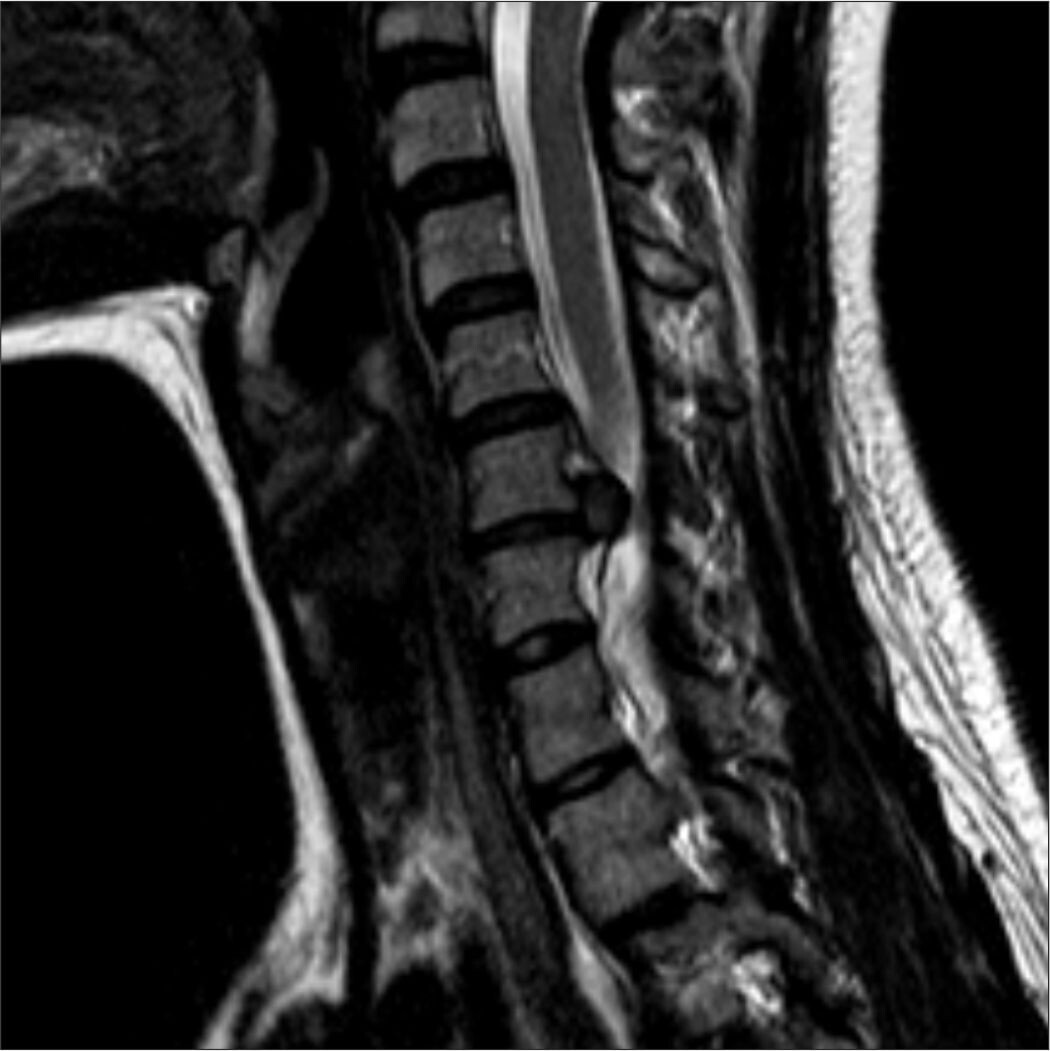

Несколько лет назад невролог направил на МРТ, где выяснилось, что в шейном и грудном отделе имеются протрузии и грыжи межпозвоноковых дисков.

Фото Яндекс Картинки